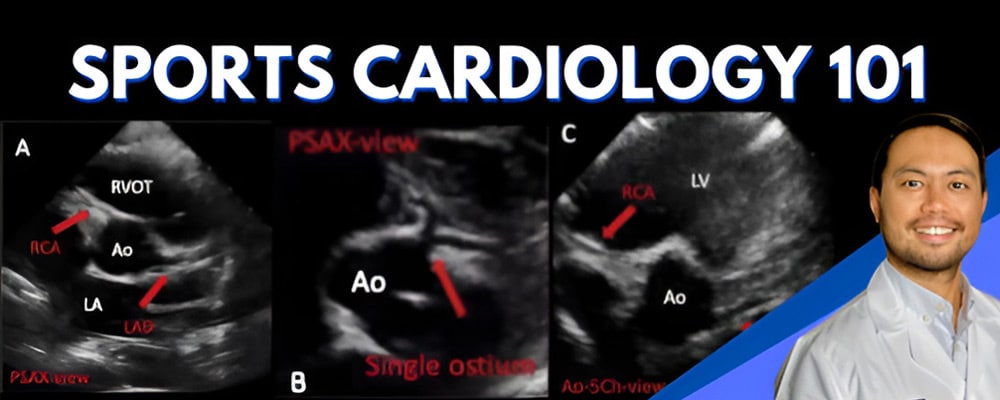

Acute Coronary Syndrome [Case Review]

Dr. Mohan navigates a real-life case of ACS, so you canlearn the key steps in EKG interpretation for treatmentand intervention!